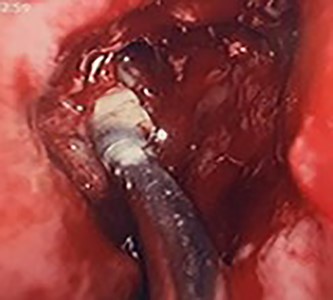

Flexible nasendoscopy offered little in terms of diagnostic benefit. An exam under anesthetic with a view to removing the ectopic tooth via endoscopic sinus surgery was warranted. Right middle turbinate trimming along with a right maxillary antrostomy was performed. The tooth was immediately identified at the antrum as depicted in Figs 4–6. The bony capsule of the tooth was entered and, on manipulation, a second ectopic tooth was identified (Fig. 7) both of which were removed en bloc. The cystic component within the maxillary sinus was marsupilized and extracted. The sinus cavity can be viewed with the utilization of 70° endoscope (Fig. 8). This facilitated bipolar cautery of the base of the cyst and confirmed the absence of an oroantral fistula.

Intra-operative image of the ectopic tooth at the right osteomeatal complex.

Intra-operative image of the ectopic tooth at the right osteomeatal complex, with curved suction facilitating enucleation.